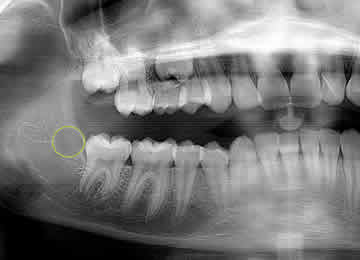

Zero3 technology has built-in controls to assure that the 3TBA procedure results in gently warming the targeted tooth bud (circled) from the center outwards to reduce the risk of adversely effecting adjacent tissue while clinically inducing 100% molar agenesis.

Zero3 technology accurately positions the center of the ablation in the center of the tooth bud.